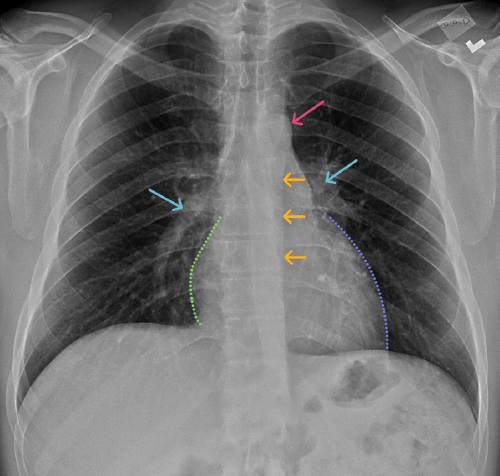

Chest

Chest

Chest radiograph & CT anatomy

Chest

Chest

Chest radiograph & CT anatomy